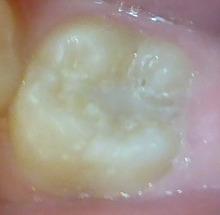

下の写真は12歳の男の子です。

通常は 麻酔をして タービンと呼ばれる

ドリルで、黒い部分を削り取ります。